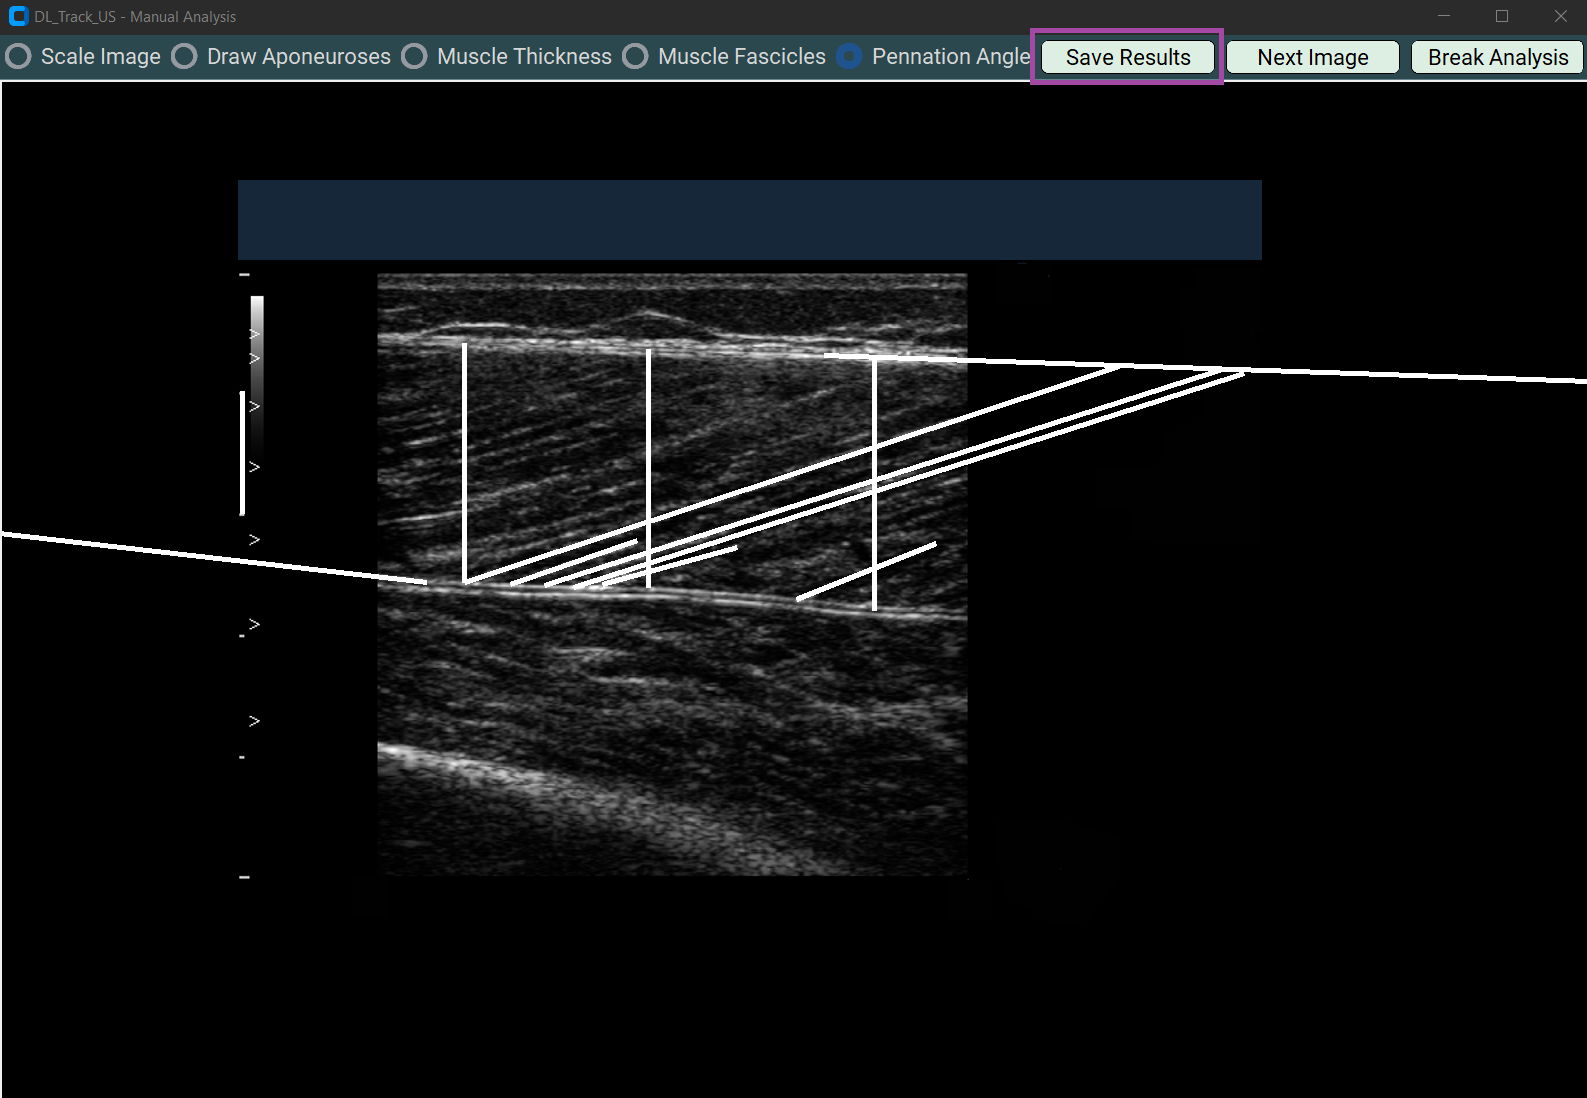

5.1 Saving Results¶

- Press the Save Results button after finishing each image.

- It saves:

- An Excel file (

Manual_Results.xlsx) - A screenshot of your drawing.

Saved results are stored in DL_Track_US_example/images_manual.

5.2 Going to Next Image¶

- Click the Next Image button to proceed.

- Always save results first before moving to the next image!